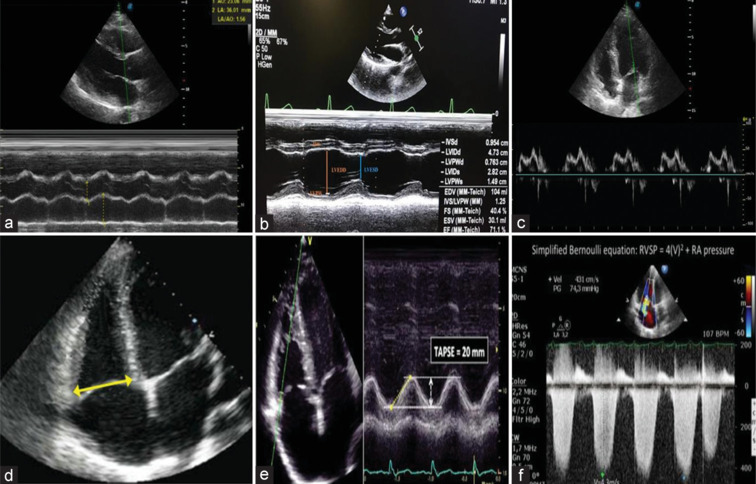

Results: Right ventricular basal diameter was significantly higher in groups chronic kidney disease (CKD) V and HD than control. Right ventricle tricuspid annular plane systolic excursion (RV TAPSE) and RV tissue Doppler imaging(S') were significantly lower in CKD Group V than HD and control group. Pulmonary HTN is present in 22% of renal patients with significantly higher prevalence in HD group. There was a positive correlation between the estimated glomerular filtration rate (eGFR) and RV TAPSE and between eGFR and RV (S') of CKD IV and CKD V groups. There was a negative correlation between RV TAPSE and pulmonary arterial systolic pressure by echocardiogram of the studied groups. There was a positive correlation between RV TAPSE and RV (S') of the studied groups.

Conclusions: HD patients showed better RV systolic indices than CKD Stage 5 patients. Pulmonary HTN, although present in all stages of CKD, showed higher prevalence in HD patients.